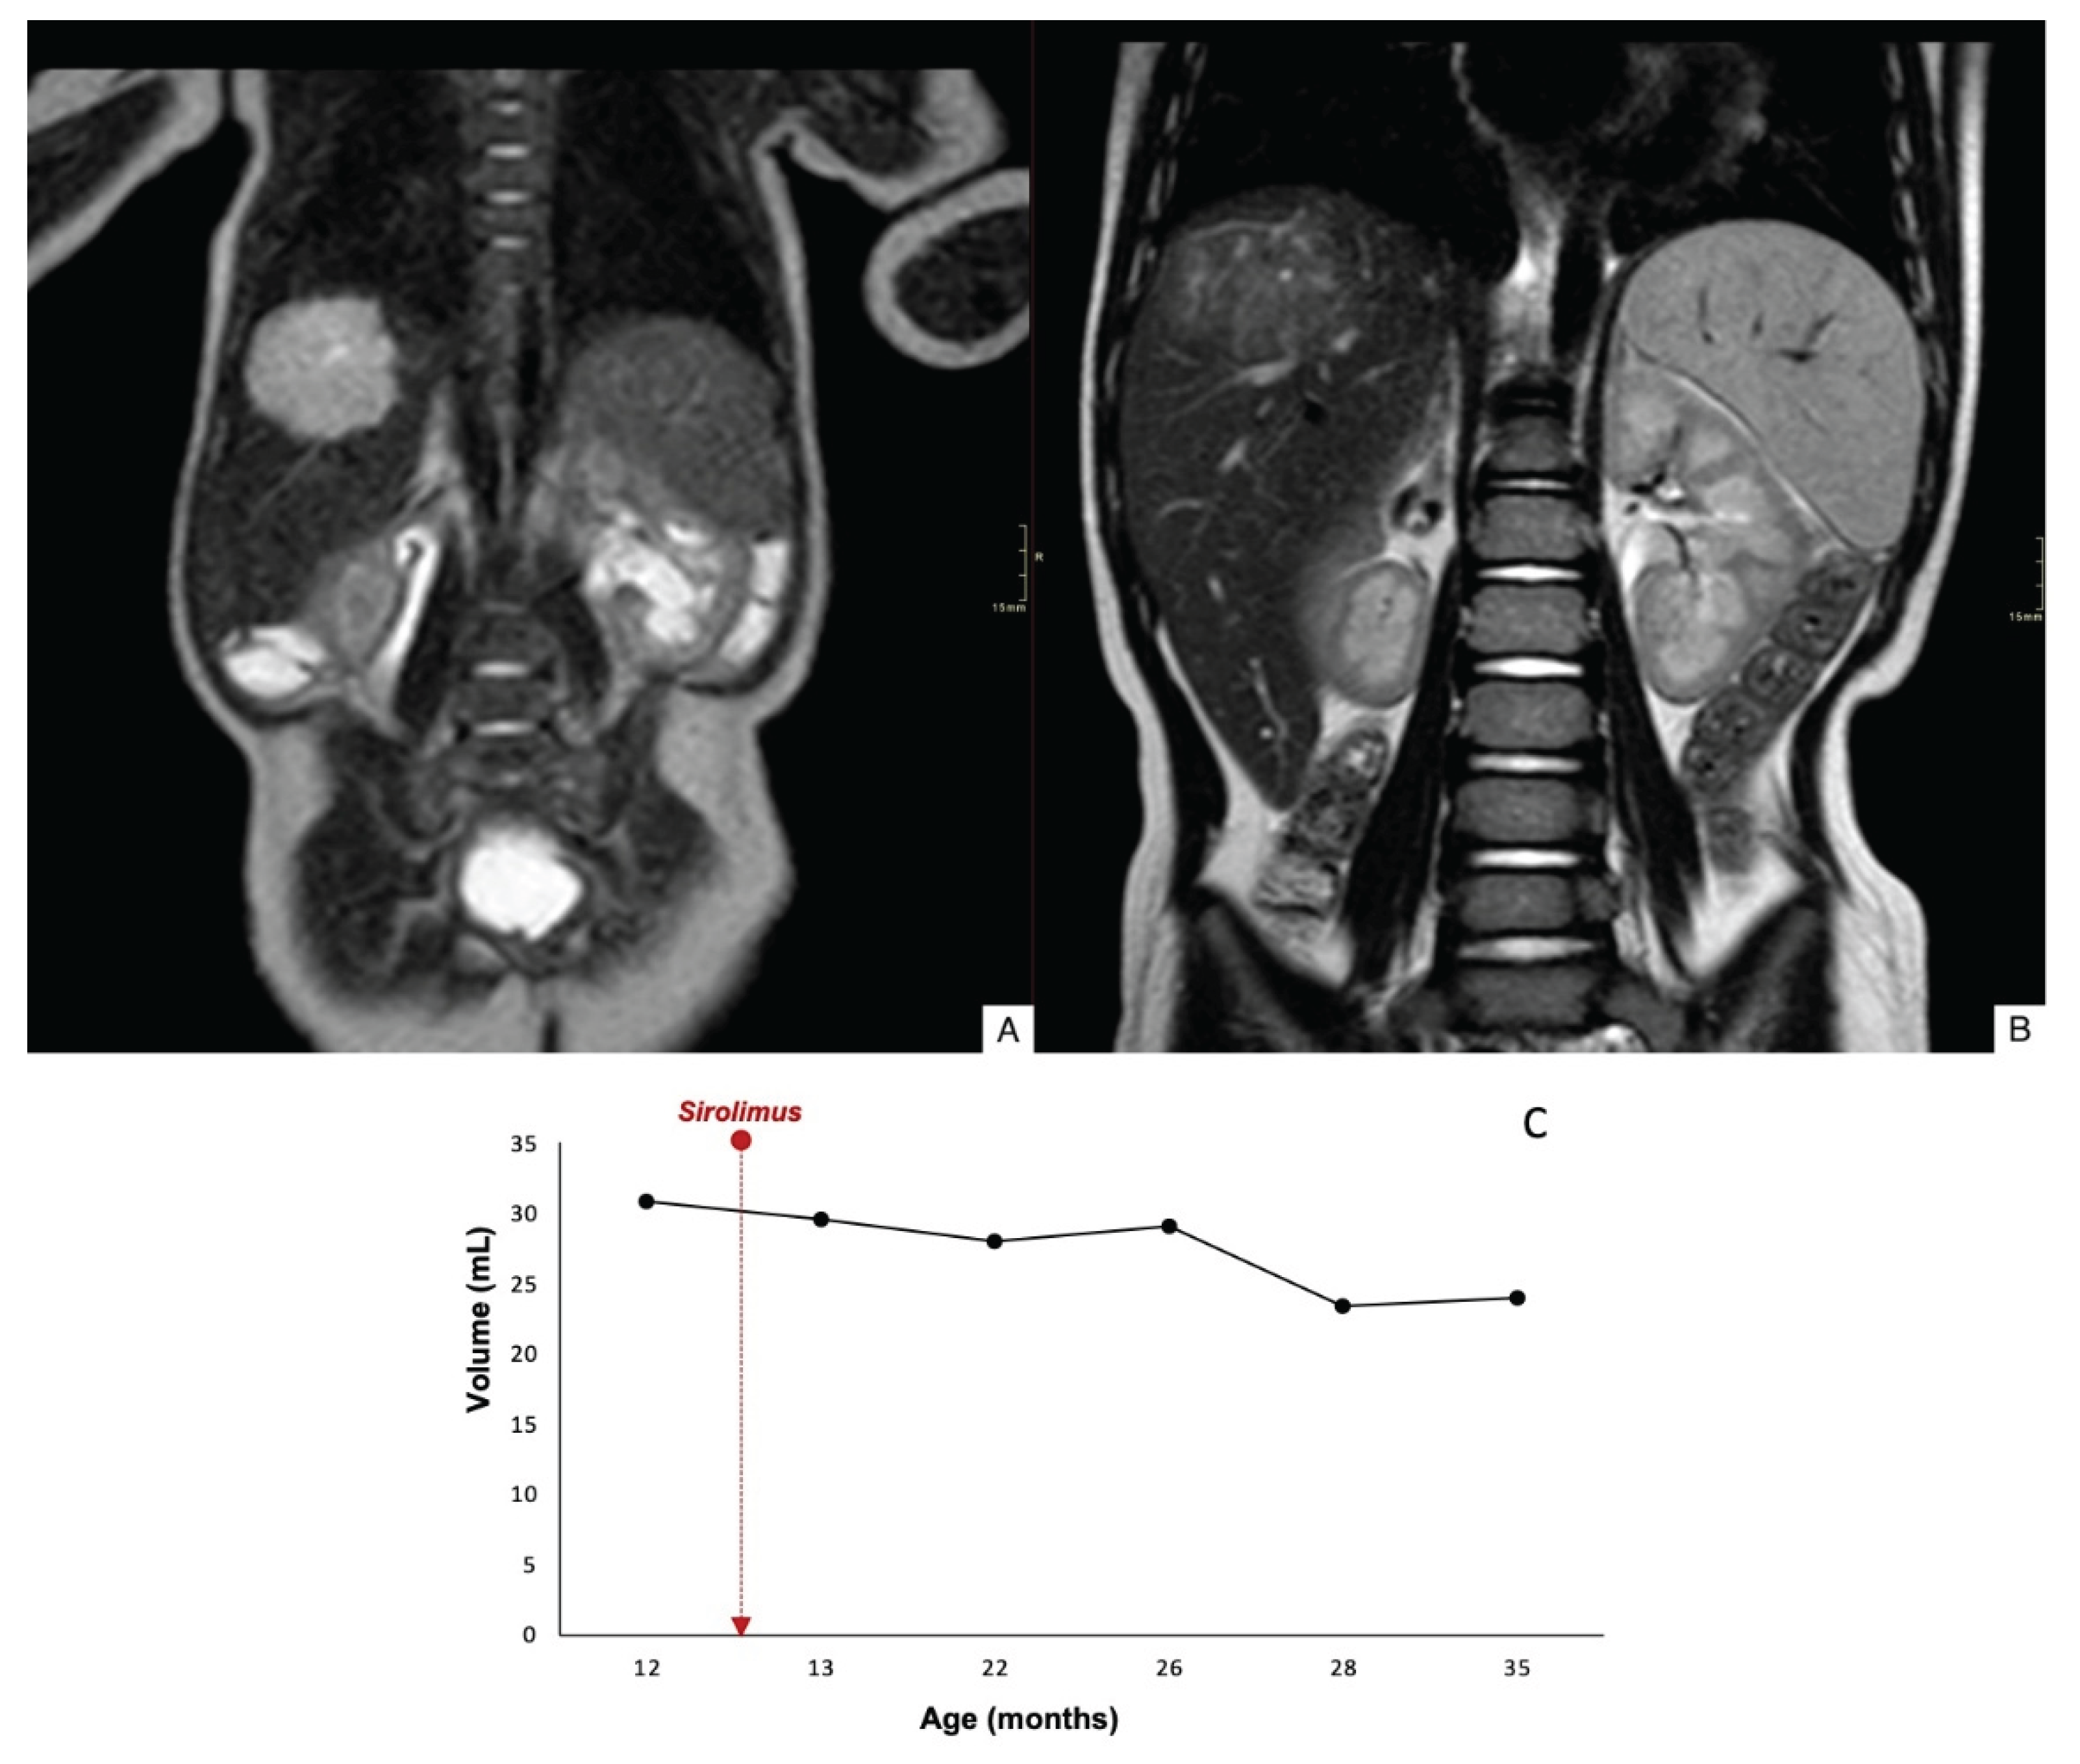

| 2 | 3,7 x 4,6 x 3,4 >4cm |

12 | Stable | Stable | 45 | No | Yes | No | 56 |